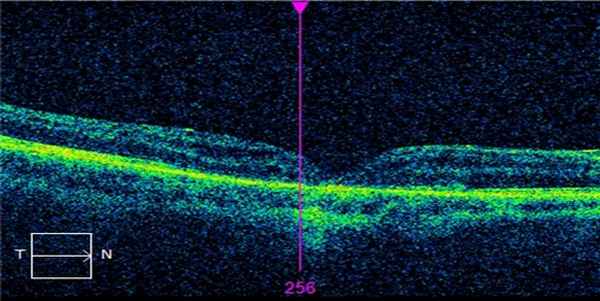

До операции. Макулярный разрыв более 1000мкн.

После операции. Разрыв закрыт.

Нами сделан вывод, что при хирургии макулярного разрыва 3 и 4-й стадий предпочтительнее использовать силиконовую тампонаду.

Ее преимущества — минимизация риска разблокирования разрывов при завершении силиконовой тампонады в стандартные сроки, сохранение адаптации разрыва при более длительной тампонаде.